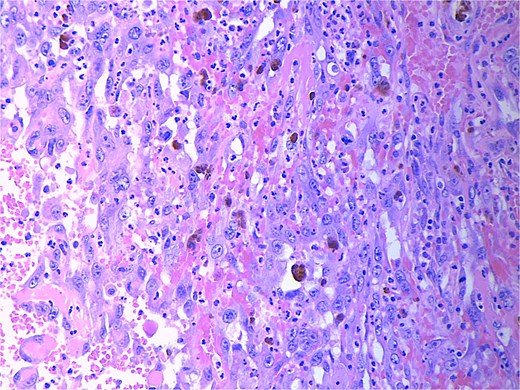

Final pathology revealed an angiosarcoma of the adrenal gland. Sections showed a predominantly hemorrhagic and necrotic mass with residual vascular forming channels within the adrenal gland (Fig. 2). Cells were pleomorphic spindled to epithelioid and atypical (Figs 3 and 4), with a mitotic count of 12/10 high-power fields. Immunohistochemistry showed positivity for ERG (Fig. 5), CD34, and focal pankeratin and negativity for SF-1, SOX10, Cathepsin-K, and chromogranin. There was no lymphatic or vascular invasion identified, and the margins were uninvolved by the tumor. The left kidney was negative for tumor, and the background adrenocortical parenchyma was benign.

High power magnification (40×) H&E showing malignant cells forming vascular channels with atypia.